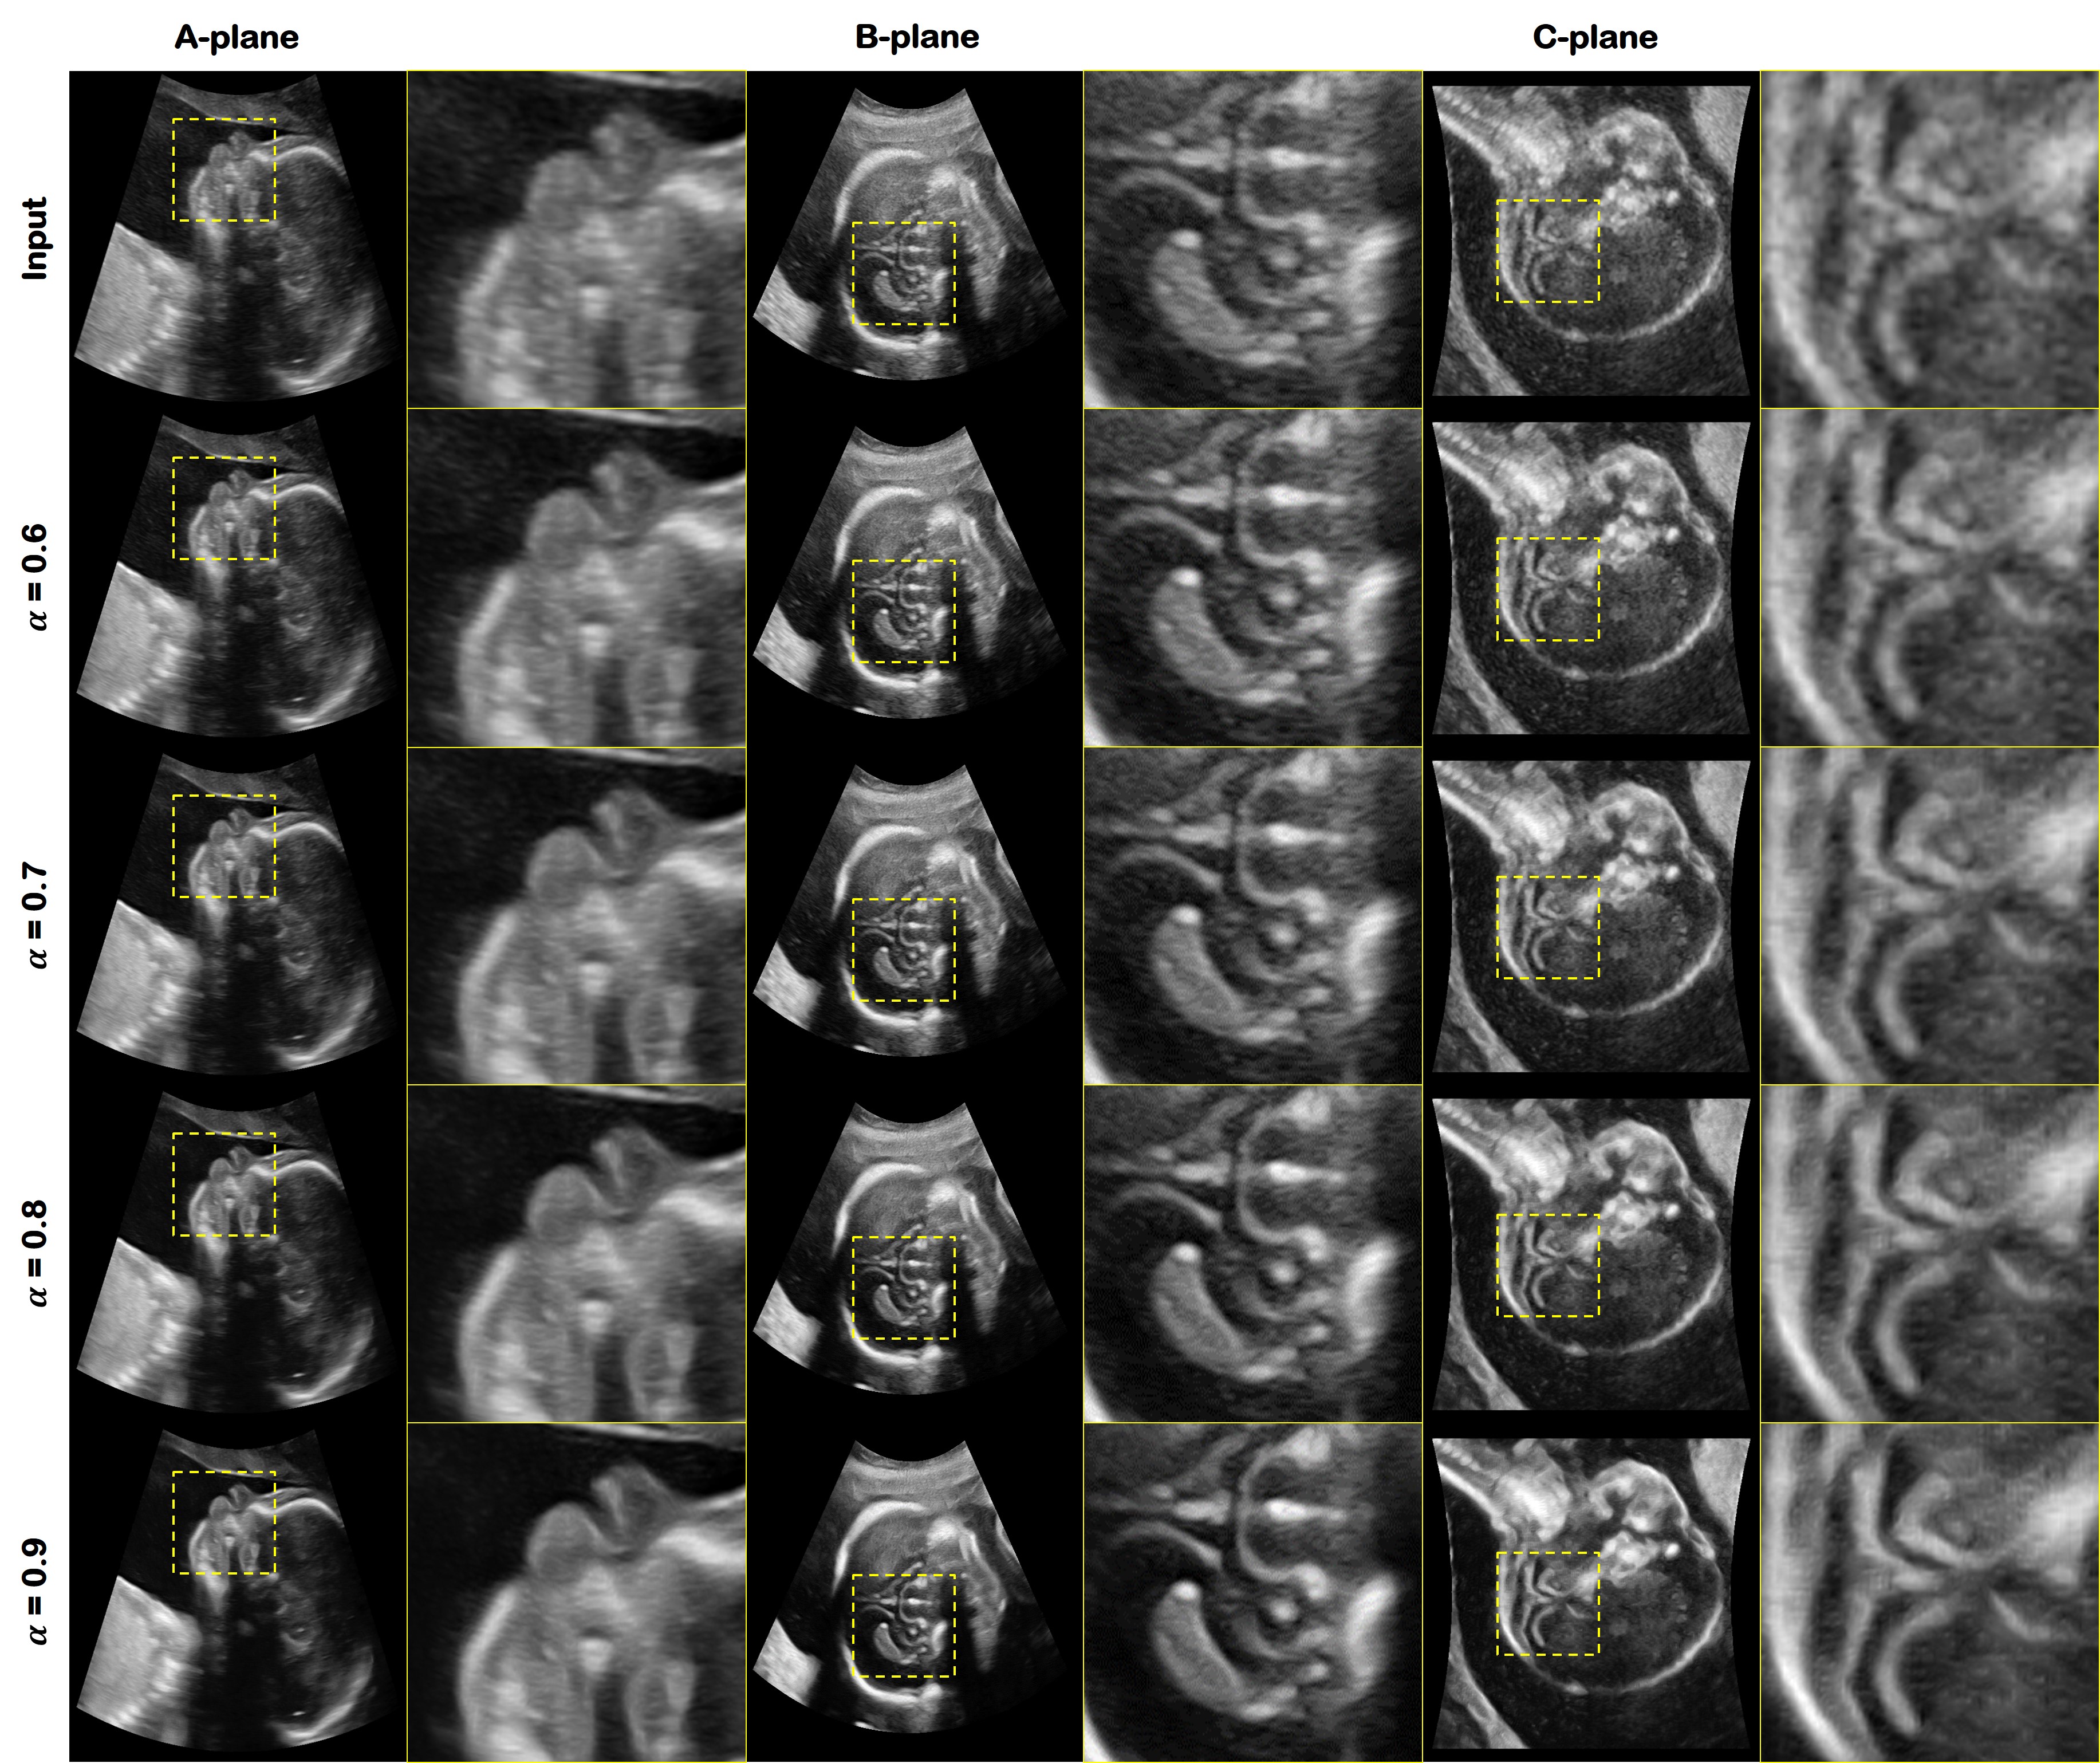

To validate our proposed method, we applied our algorithms to real gynecology (GYN) clinical data sets. The results are shown in Fig. 5. The first row shows the input image. From the second to the last row, each row refers to the outputs of the proposed network with different α𝛼\alpha values. The left column is the A-plane, which is cut along the elevation axis, the second and third are the B-plane and the C-plane, respectively, which are cut along the lateral axis and axial axis, respectively. We have presented the images from α=0.6𝛼0.6\alpha=0.6 to α=0.9𝛼0.9\alpha=0.9, the change being clearly visible.

As shown in the Fig. 5, the input image is gradually changed to the target style depending on α𝛼\alpha, which can be again verified from the magnified area. The follicle boundaries are not clear from the input image. However, the proposed method connects the structures smoothly. The contrast is increased so that the follicle borders can be clearly seen. In addition, tearing artifacts in the B-plane is well suppressed and their resolution appears to be increased. The side lobe artifacts, which is one of the basic artifact in US image, are clearly visible in the input image. On the other hand, the proposed method has suppressed it and its boundaries become sharp and easily discernible as the value of α𝛼\alpha is increased.

4.4 Obstetric Results

We tested our algorithm with the OB images that were not used in network training. The goal was to demonstrate that our method can be robustly applied to a wide range of datasets.

In Fig. 7, we have visualized the head bone of the fetus. Each row denotes the input and its output of the proposed method with different α𝛼\alpha values. Each column shows the A-, B- and C- planes. As shown in Fig. 7, the input image has ambiguous boundaries, in particular its structure in the head bone is not easy to see. However, the result of the proposed method is that the internal structure is more visible than the input image. In addition, its boundary becomes sharp as the value of α𝛼\alpha is increased. In particular, the side-lobe artifact is well suppressed according to the α𝛼\alpha variation.